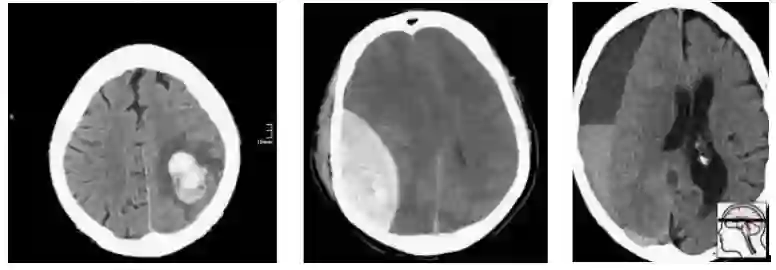

最近,一个新的大型CT脑扫描数据集被发布,其目的是训练模型以检测颅内出血。

在这一人群中,我们有相当合理的“临床”病例组合。3例脑内出血(可能与高血压或中风有关),2例创伤性出血。

现在让我们对这个群体进行抽样,以构建我们的测试集:

随机地,我们抽样得到的大部分是轴外出血。在这项测试中表现良好的模型不一定能在真实的患者身上发挥同样的效果。事实上,你可能期望一个擅长轴外出血而牺牲脑内出血的模型获胜。